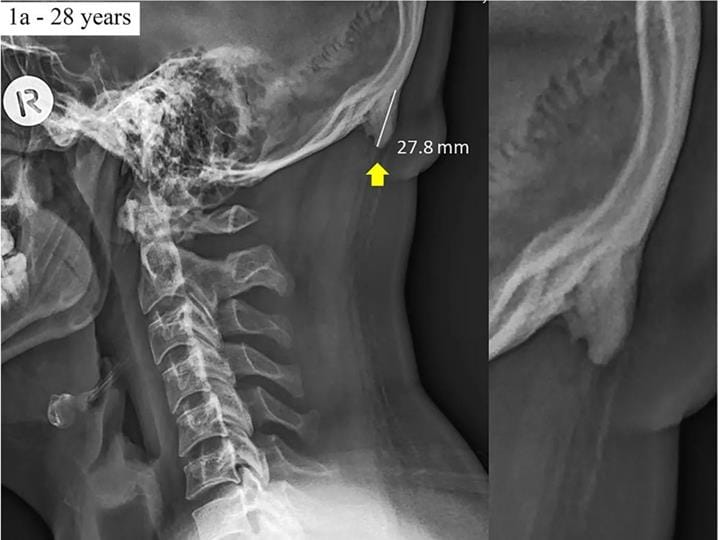

Kafatasında minik şişlikler çıkmasına tıpta EEOP adı veriliyor. Ancak bu şişlikler eskiden geç yaşlarda kendini belli ediyor. Yapılan bir araştırmaya göre milenyum çağında yetişen çocukların kafatasında minik şişlikler çıktığı belirlenmiş. Hatta son yıllarda 18-30 yaş aralarında daha sık görülmeye başlanmış.

Tıpta EEOP adı verilen kafatasında minik şişlikler oluşması son zamanlarda arttığını belirleyen araştırmacılar yaptığı açıklamada bunun tehlikeli olmadığını işaret ediyor. Bu minik şişliklerin oluşmasına neden olanın, telefon ve bilgisayar kullanırken boynumuzun sürekli olarak aşağı ve yukarı bakması olarak tespit edilmiş.